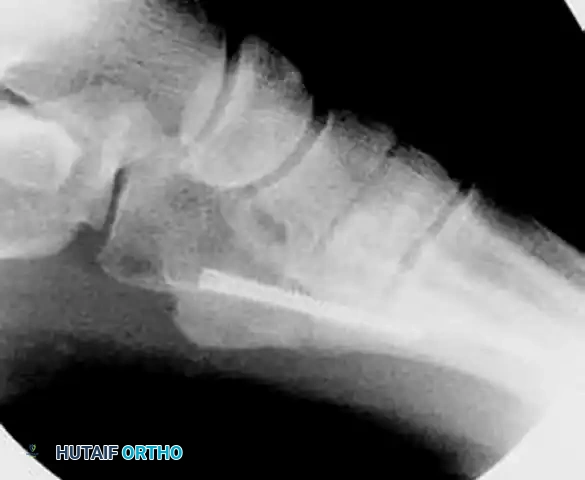

In cases of delayed union or nonunion, advanced imaging such as a Computed Tomography (CT) scan may be warranted to assess the extent of medullary sclerosis and to precisely measure the canal diameter. The medullary canal of the fifth metatarsal is not perfectly straight; it exhibits a lateral and plantar bow. Preoperative templating is critical to select a screw diameter that achieves cortical purchase without causing iatrogenic lateral cortical blowout.

Achieving the correct starting point is the most critical step of the operation. Because of the lateral bow of the metatarsal, starting directly on the tip of the tuberosity will result in a trajectory that breaches the medial cortex.

- The "High and Inside" Rule: The optimal starting point is slightly dorsal and medial to the anatomic center of the tuberosity.

- Guidewire Insertion: Use a stout guide wire (typically 1.4mm or 1.6mm) to find the medullary canal. This can be technically demanding. The wire must lie almost parallel to the hindfoot and the plantar aspect of the foot.

- Fluoroscopic Confirmation: Advance the wire under multi-planar fluoroscopy. Ensure the wire passes the fracture site and sits centrally within the narrowest portion of the diaphysis (the isthmus).